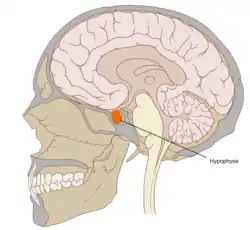

Hypophyse

Die Hypophyse (auch griechisch-lateinisch Hypophysis cerebri und kurz Hypophysis, von altgriechisch ὑπόφυσις hypóphysis „das unten anhängende Gewächs“) oder Hirnanhangdrüse, lateinisch Glandula pituitaria, ist eine an der Basis des Gehirns „hängende“, etwa erbsengroße Hormondrüse, die vom Hypothalamus gesteuert wird und der eine zentrale übergeordnete Rolle bei der Regulation des Hormonsystems im Körper zukommt. Sie ist eine Art Schnittstelle, mit der das Gehirn über die Freisetzung von Hormonen Vorgänge wie Wachstum, Fortpflanzung und Stoffwechsel reguliert. Die Hypophyse sitzt dem Türkensattel (Sella turcica), einer knöchernen Vertiefung der mittleren Schädelgrube auf Höhe der Nase, auf.